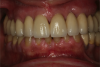

Fig 12. Frontal view (Fig 12) and occlusal view (Fig 13) of clinical application of dual-axis principles. (Images courtesy of Costa Nicolopoulos, BDS)

Figure 12

Fig 13. Frontal view (Fig 12) and occlusal view (Fig 13) of clinical application of dual-axis principles. (Images courtesy of Costa Nicolopoulos, BDS)

Figure 13